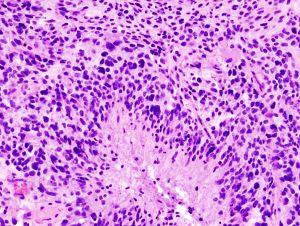

قد يتم إجراء خزعة باستخدام إبرة بالتوضيع التجسيمي للأورام الدبقية في المناطق التي يصعب الوصول إليها أو المناطق الحساسة جدًا داخل الدماغ التي قد تتضرر من أي عملية أكثر توسعًا. خلال خزعة إبرة التوضيع التجسيمي، يحفر جراح الأعصاب ثقبًا صغيرًا في الجمجمة. ثم يتم إدخال إبرة رفيعة من خلال ثقب. تتم إزالة الأنسجة من خلال الإبرة، والتي كثيرًا ما يتم توجيهها باستخدام التصوير المقطعي المحوسب أو المسح الضوئي بالتصوير بالرنين المغناطيسي. ثم يتم تحليل عينة الخزعة تحت المجهر لتحديد ما إذا كانت سرطانية أو حميدة.

تعد الخزعة هي الطريقة الوحيدة لتشخيص ورم الدماغ بشكل نهائي وإمدادك بتشخيص لتوجيه قرارات العلاج. واستنادًا إلى هذه المعلومات، يمكن لطبيب الأمراض تحديد درجة الورم في الدماغ أو مرحلته.

وتنقسم الأورام إلى أربع درجات حيث تكون أورام الدرجة الأولى الأبطأ نموًا وأكثرها خلايا حميدة وتحتوي أورام الدرجة الرابعة على أكثر الخلايا السرطانية شذوذًا وعنفًا.